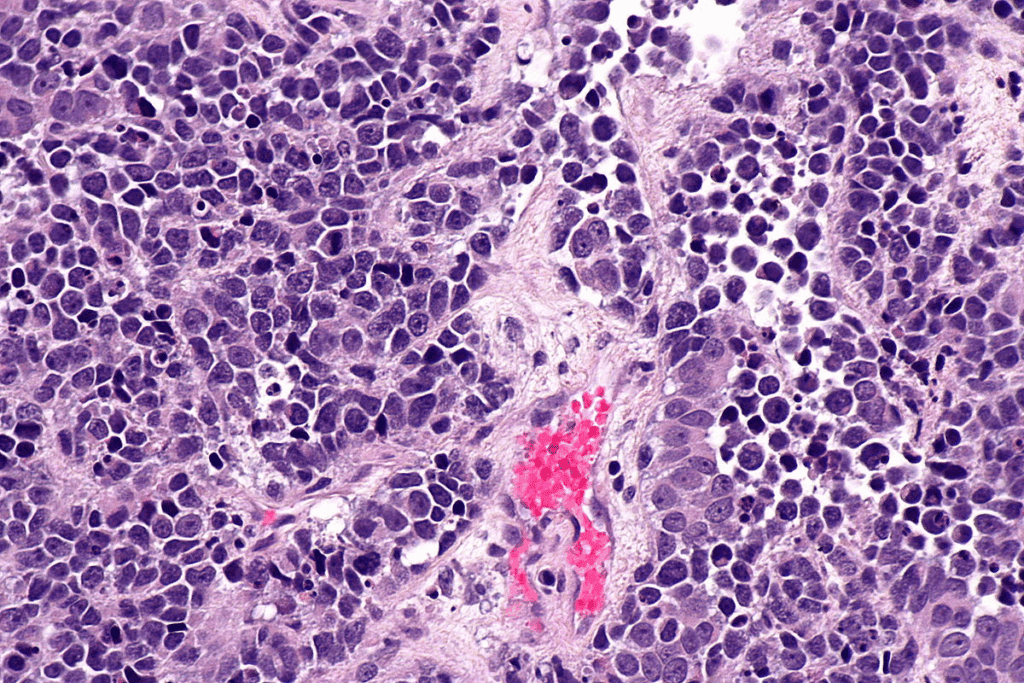

Types and Development of Bladder Cancer

Bladder cancer is divided into types based on where it starts. The most common is transitional cell carcinoma, or urothelial carcinoma. It begins in the bladder’s lining cells. Less common types include squamous cell carcinoma and adenocarcinoma, each with its own risk factors.

Bladder cancer develops from genetic changes in bladder cells. These changes cause cells to grow out of control. Many factors can influence this, like genetics, environment, and lifestyle.

Tumor Grade and Molecular Characteristics

The tumor’s grade is very important. High-grade tumors grow and spread faster, which can make the prognosis worse.

What makes up the tumor, like genetic changes, also matters. Scientists are working on new treatments that target these changes.